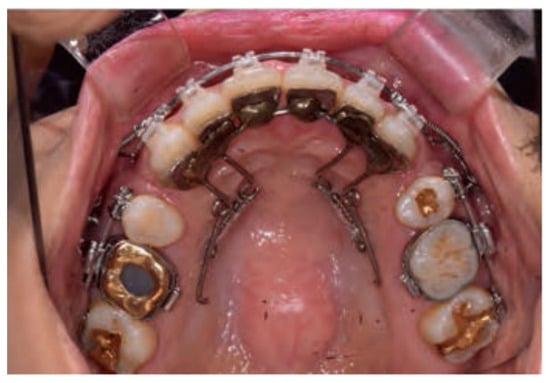

The APLR basically consists of a C-lingual retractor bonded to the lingual surfaces of the six anterior teeth, lever arms, posterior splints, and posterior tubes, which act as pathways for the guide bar. The lever arms are soldered to the anterior splint, and the posterior tubes are soldered to the posterior splint. A guide bar with a diameter of 0.036-in extending from the lever arm passes and slides through the posterior tube (Figure 7) [1,5]. Friction in the APLR is minimized compared to conventional lingual brackets as the friction in the APLR occurs only between the guide bar and the posterior tube during retraction.

Figure 7.

Antero-posterior Lingual Retractor (APLR) appliance.

- (1)

- Anterior Segment

The anterior part of the APLR was similar to that of the CLR. In addition, the 0.036-in stainless steel guide bar, soldered to the lever arm or attachment pad extends posteriorly into the posterior tube [1,5].

- (2)

- Posterior Segments

The posterior connecting wire is soldered to the posterior attachment pad to be positioned on the second premolar, first and second molar to form a posterior splint. A posterior tube 1 mm in diameter, typically parallel to the occlusal plane is soldered to the first molar area of the posterior splint and acts as a sliding path. The guide bar soldered to the anterior segment passes through the posterior tube and the clearance between the guide bar and posterior tube is approximately 0.1 mm [1,5].

- (3)

- Accessory Parts

The transverse dimension is controlled by adding a TPA. It is soldered to the extended arm which is connected to the first molar pad. In some cases, additional hooks are added to the TPA for posterior intrusion or torque control [1].

- (4)

- TSADs

Generally, miniscrews or C-palatal plate are placed in the midpalatal area for torque and vertical control of anterior teeth [5].

APLR can adjust the three-dimensional control of anterior teeth with the anterior lever arm, guide bar, posterior tube, and position of TSADs. As shown in Figure 10, when force is applied from the lever arm to the TSADs in the midpalatal area, the anterior teeth are intruded and retracted with torque control. The posterior teeth are intruded by the kinetic energy generated when the force direction and the guide bar are not parallel. Resultantly, the mandible is autorotated counterclockwise, and the occlusal plane is maintained or flattened [34,35]. Therefore, APLR is effective when applied to hyperdivergent Class II patients with a gummy smile or uprighted maxillary incisors [1,5,24,34,35].

Figure 10.

Biomechanics of the antero-posterior lingual retractor (APLR).

Based on the combination of the length of the extended arms and the location of TSADs, the effective vertical movement of the anterior teeth is possible with adequate torque control [1,5,24]. A heavy guide bar connected to the posterior segments effectively controls the retraction vector to prevent anterior torque loss [34,35]. The posterior tube also controls the amount of intrusion of the anterior teeth. A previous study suggested that the angular change of the posterior tube of the APLR resulted in a difference in the intrusion amount of the anterior teeth [35]. If the angulation of the posterior tube was parallel to the maxillary occlusal plane, the anterior segment showed bodily movement without angulation change (Figure 11B) [34,35]. When the tube angulation was tipped disto-occlusally, the intrusion amount of the maxillary anterior teeth increased (Figure 11C). Therefore, the maxillary anterior teeth in patients with an excessive gingival display can be effectively controlled by changing the angulation of the tube [35].